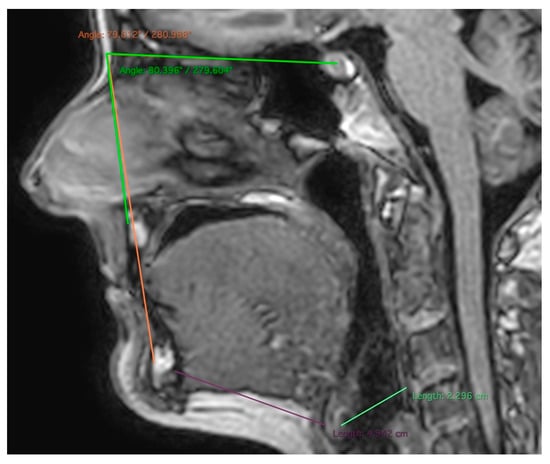

| SNA angle | A: 0.485 (0.142, 0.713) | C: 0 | E: 0.515 (0.287, 0.858) |

| SNB angle | A: 0.702 (0.422, 0.849) | C: 0 | E: 0.298 (0.151, 0.578) |

| Mandibular–hyoid distance | A: 0 | C: 0.569 (0.312, 0.746) | E: 0.431 (0.254, 0.688) |

| Hyoid–cervical tangent distance | A: 0 | C: 0.685 (0.510, 0.805) | E: 0.315 (0.195, 0.490) |

| Soft palate length | A: 0 | C: 0.629 (0.437, 0.765) | E: 0.371 (0.235, 0.563) |

| Soft palate thickness | A: 0.666 (0.442, 0.804) | C: 0 | E: 0.334 (0.196, 0.558) |

| Soft palate area | A: 0 | C: 0.633 (0.444, 0.768) | E: 0.367 (0.232, 0.556) |